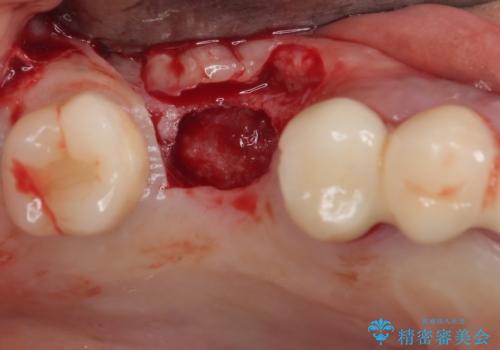

- インプラントが脱落してしまったとのことで来院された患者様です。

歯肉は綺麗に治癒しており、インプラント埋入に十分な骨があったため、速やかにインプラント埋入を行うこととしました。

インプラント埋入の状態が良ければ即日で仮歯を装着し、十分な生着が確認され次第、オールセラミッククラウンにて補綴治療を行うこととしました。

インプラントの初期固定も埋入後の生着もスムーズであったので、埋入から3ヶ月で無事に治療を終えることができました。